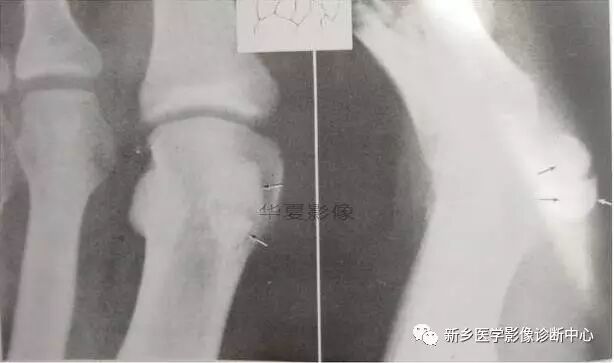

5、拇趾双子骨拇趾双子骨。类似骨折,注意鉴别。

6、骨骺分段征象

• 骨骺分段征象之一:

• 骨骺分段征象之二: